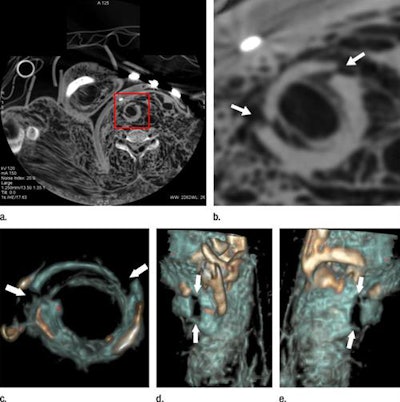

Cricoid cartilage of a 27-year-old woman who died of strangulation, visualized in an axial cervical postmortem CT scan (a, b) and volume-rendered 3D reconstructions (c-e). CT angiography revealed a bilateral fracture that proved difficult to demonstrate clearly with autopsy.For some cases, the interpretation of the autopsy results concerning cause of death and the events leading up to it would have been incomplete or wrong without postmortem CT angiography, Grabherr said. This is why, in most centers, the forensic pathologist and radiologist work together.